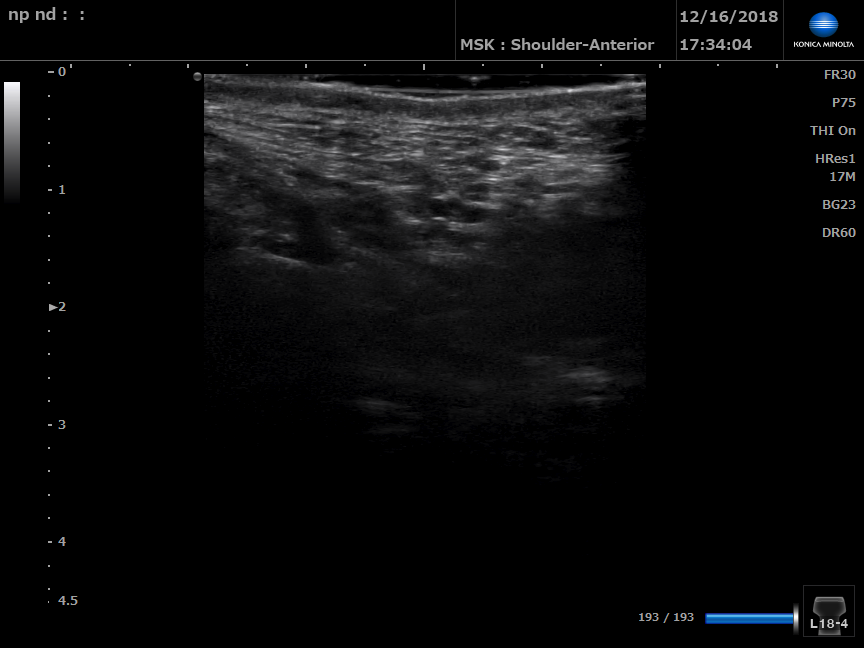

B Mode ultrasound of left perineal body

B Mode ultrasound of right perineal body